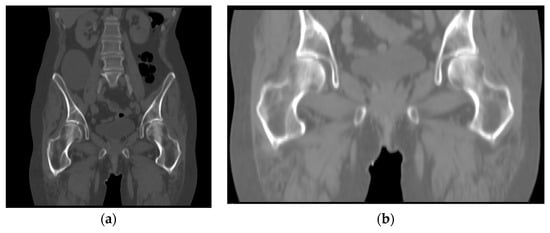

3.4. Measurement of Implant Displacement Based on Conventional Methods

In this subsection, to verify our proposed measurement of implant displacement’s validity, we used the reference point-based distance measurement method described in [18]. We define the point on the outer surface of the Lesser trochanter farthest from the centerline of the medullary cavity as reference point A. As shown in Figure 13a–c, all steps to locate point A were performed entirely using the three planes in the CT images, and no 3D femur model was used to assist in localization. Figure 13d is used to assist in showing the position of the reference point in the CT image.

Figure 13.

Locating reference point A in the CT image: (a) reference point located in the axial plane; (b) reference point located in the sagittal plane; (c) reference point located in coronal plane; (d) display reference point in the 3D model.

Point A is used as the origin, and a new coordinate system is formed with the intersecting lines of the planes, axial plane (green), coronal plane (blue), and sagittal plane (red), as shown in Figure 14. The coordinates of the target object are measured in the new coordinate system, and the Euclidean distance is calculated using the formula

where (, , ) and (, , ) represent the coordinates of the same point in the two CT image sequences, respectively.

Figure 14.

Create coordinate system for measurement.

To reduce the measurement error, we measure the coordinates of each point three times and take the average value to plug into Equation (8).